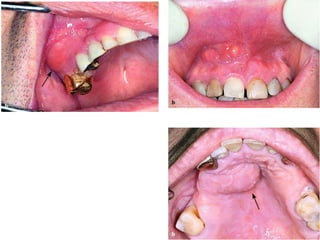

 Masticator spaceinfection  C- Pterygomandibular Space An abscess of this space is caused mainly by infection of mandibular third molars or the result of an inferior alveolar nerve block, if the penetration site of the needle is infected (pericoronitis).  Clinical Presentation.  Severe trismus and slight extraoral edema beneath the angle of the mandible are observed.  Intraorally, edema of the soft palate of the affected side is present, as is displacement of the uvula and lateral pharyngeal wall, while there is difficulty in swallowing.

• 134.

Right pterygomandibular space abscess.Note the swelling of the anterior tonsillar pillar and the deviation of the edematous uvula to the opposite side.

• 135.

Treatment. The abscess isdrained, permitting the evacuation of pus along the shaft of the instrument.